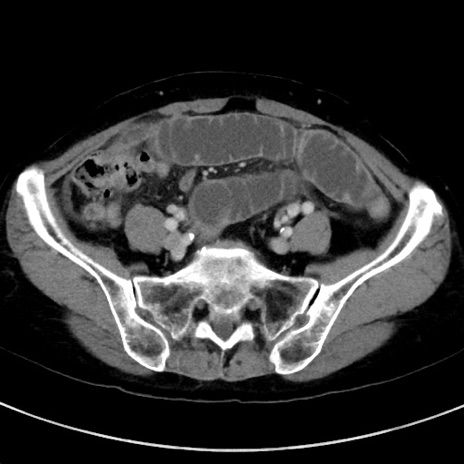

冠状断像

【症例】70歳代女性

【主訴】下腹部痛・嘔吐

【現病歴】2日前より腹痛あり。昨日嘔吐あり。症状改善しないため来院。

【既往歴】胃GISTに対して胃部分切除後。

【身体所見】BT 37.1℃、BP 128/77mmHg、腹部:平坦・軟、下腹部に圧痛あり。

【データ】WBC 10200、CRP 0.31